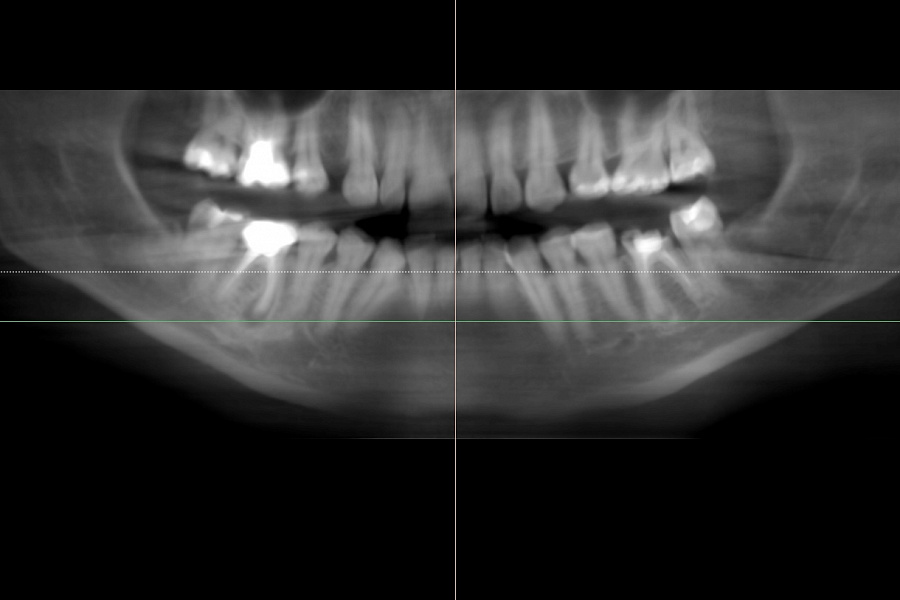

В ходе диагностики мы выяснили, что нижние шестерки вылечить невозможно. В таком случае необходимо удалить зубы и установить имплантаты.

Пациентка начала ортодонтическое лечение и за 5 месяцев до окончания лечения ей удалили нижние шестерки и поставили импланты. За месяц до конца лечения установили формирователи десны. На момент снятия брекетов были сняты слепки под постоянные коронки на имплантатах.